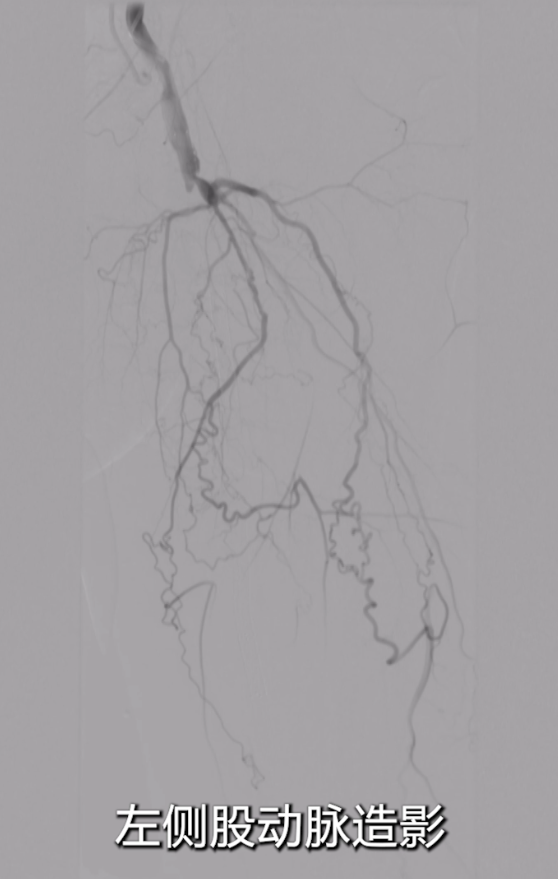

采用右侧股动脉入路,穿刺股总动脉后行基线造影;

腹主动脉及左侧股动脉造影显示:左侧股总动脉支架几乎完全闭塞,

支架长度较长(从股总动脉延伸至收肌管临近P1段),且部分遮挡股深动脉开口;膝下动脉显影稀疏,流出道条件差。